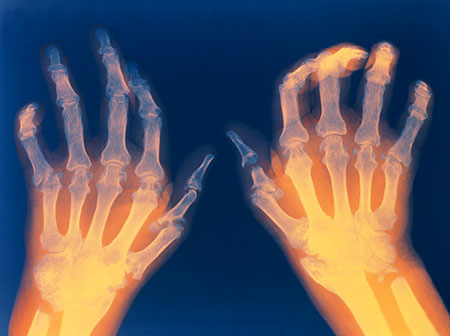

Orang dengan rheumatoid arthritis sering memiliki tingkat sedimentasi eritrosit yang meningkat (LED, atau ESR) atau C-reactive protein (CRP), yang dapat mengindikasikan adanya proses peradangan di tubuh. Tes darah umum lainnya mencari faktor rheumatoid dan antibodi peptida anti-siklik citrullinated (anti-CCP). Dokter Anda mungkin menyarankan sinar-X untuk membantu melacak perkembangan rheumatoid arthritis di persendian Anda dari waktu ke waktu. Tes MRI dan USG dapat membantu dokter menilai tingkat keparahan penyakit di tubuh Anda.